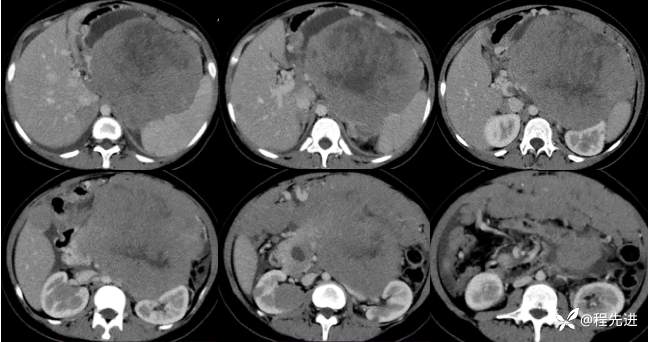

增强晚期: